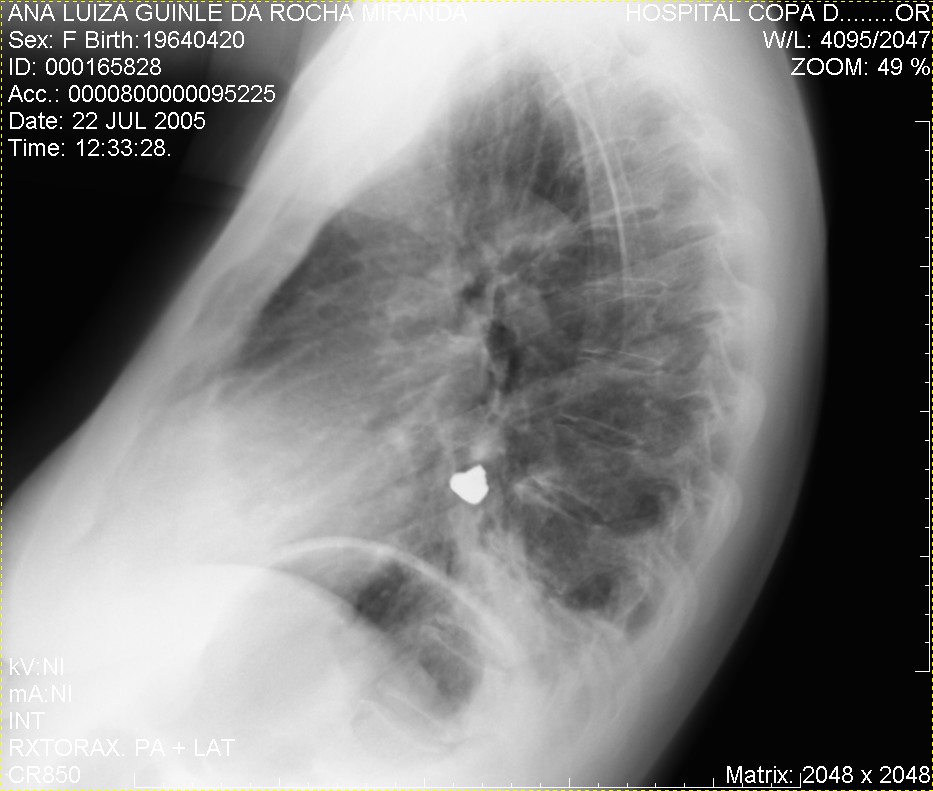

Caso relatado na Reunião de Discussão de Casos Clínicos do Hospital Universitário Prof. Polydoro Ernani de São Thiago, iniciada pelos Profs. Jorge Dias de Matos, Marisa Helena César Coral e Rosemeri Maurici da Silva, em julho de 2017. No dia 14 de junho de 2018, no auditório do HUPEST, realizou-se a apresentação e discussão do caso cujo registro é apresentado a seguir. Trata-se da discussão de onze casos em radiologia torácia, de forma interativa com a plateia, e assim ocorre também neste artigo.